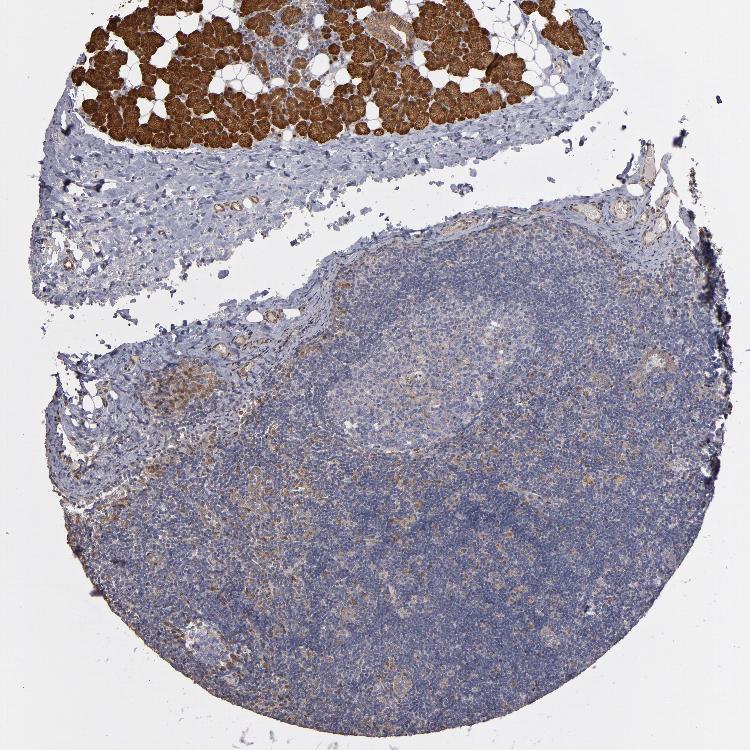

TISSUE PRIMARY DATA LYMPH NODE Show tissue menu

Lymph node

LYMPH NODE - Antibody stainingi

Antibody staining in the annotated cell types in the current human tissue is reported as not detected, low, medium, or high, based on conventional immunohistochemistry profiling in selected tissues. This score is based on the combination of the staining intensity and fraction of stained cells.

Each image is clickable and will lead to virtual microscopy that enables deeper exploration of all samples and also displays staining intensity scores, fraction scores and subcellular localization as well as patient and tissue information for each sample.

Antibody HPA002896Antibody HPA003590Antibody CAB017491

Germinal center cells LowLowNot detected

Non-germinal center cells LowNot detectedLow